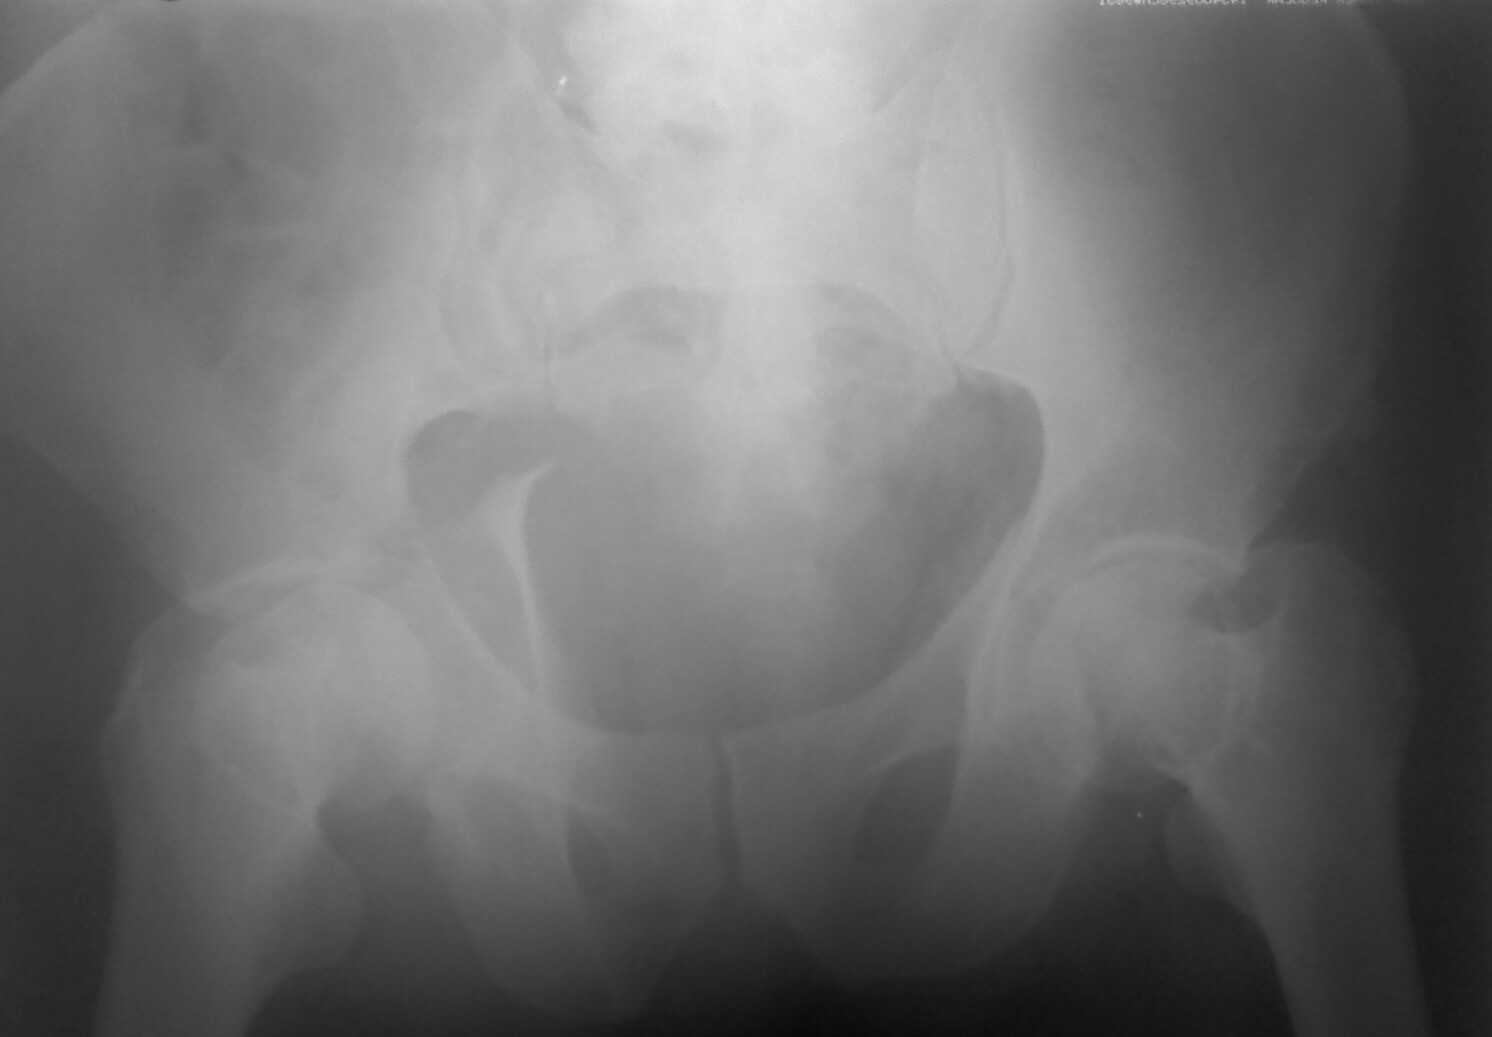

Re: Перелом вертлужных впадин

Извините, пробую еще раз